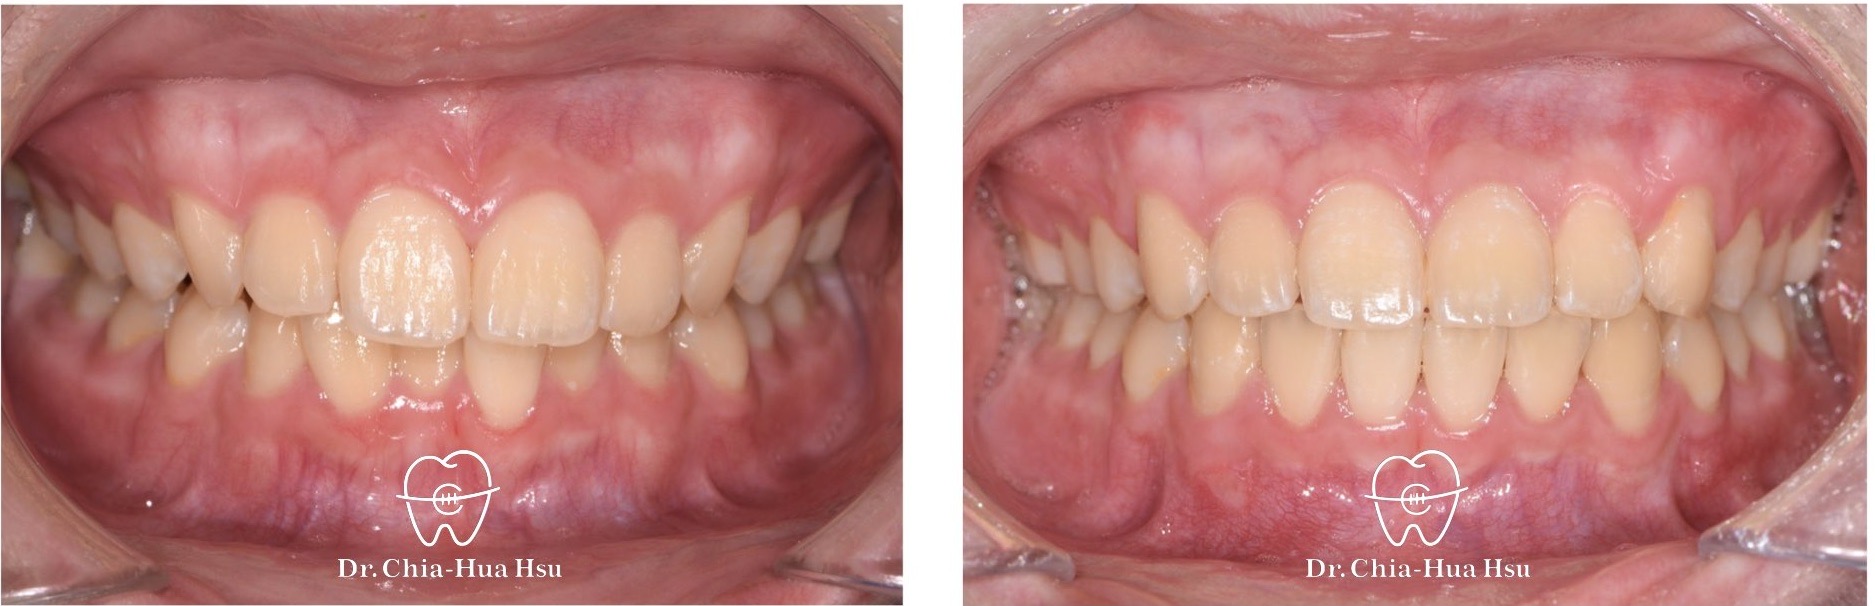

• 病患主訴:牙齒凌亂擁擠。

• 問題分析:患者是標準的骨骼一類咬合(Skeletal Class I)伴隨齒列擁擠以及咬合平面傾斜。

• 治療方式:使用傳統金屬矯正器,撐寬牙弓以獲得空間,並搭配二級橡皮筋牽引(Class II elastics)。

• 治療時間:1.5 年。

• 治療結果:齒列排齊,笑容更自信。

治療前

治療後